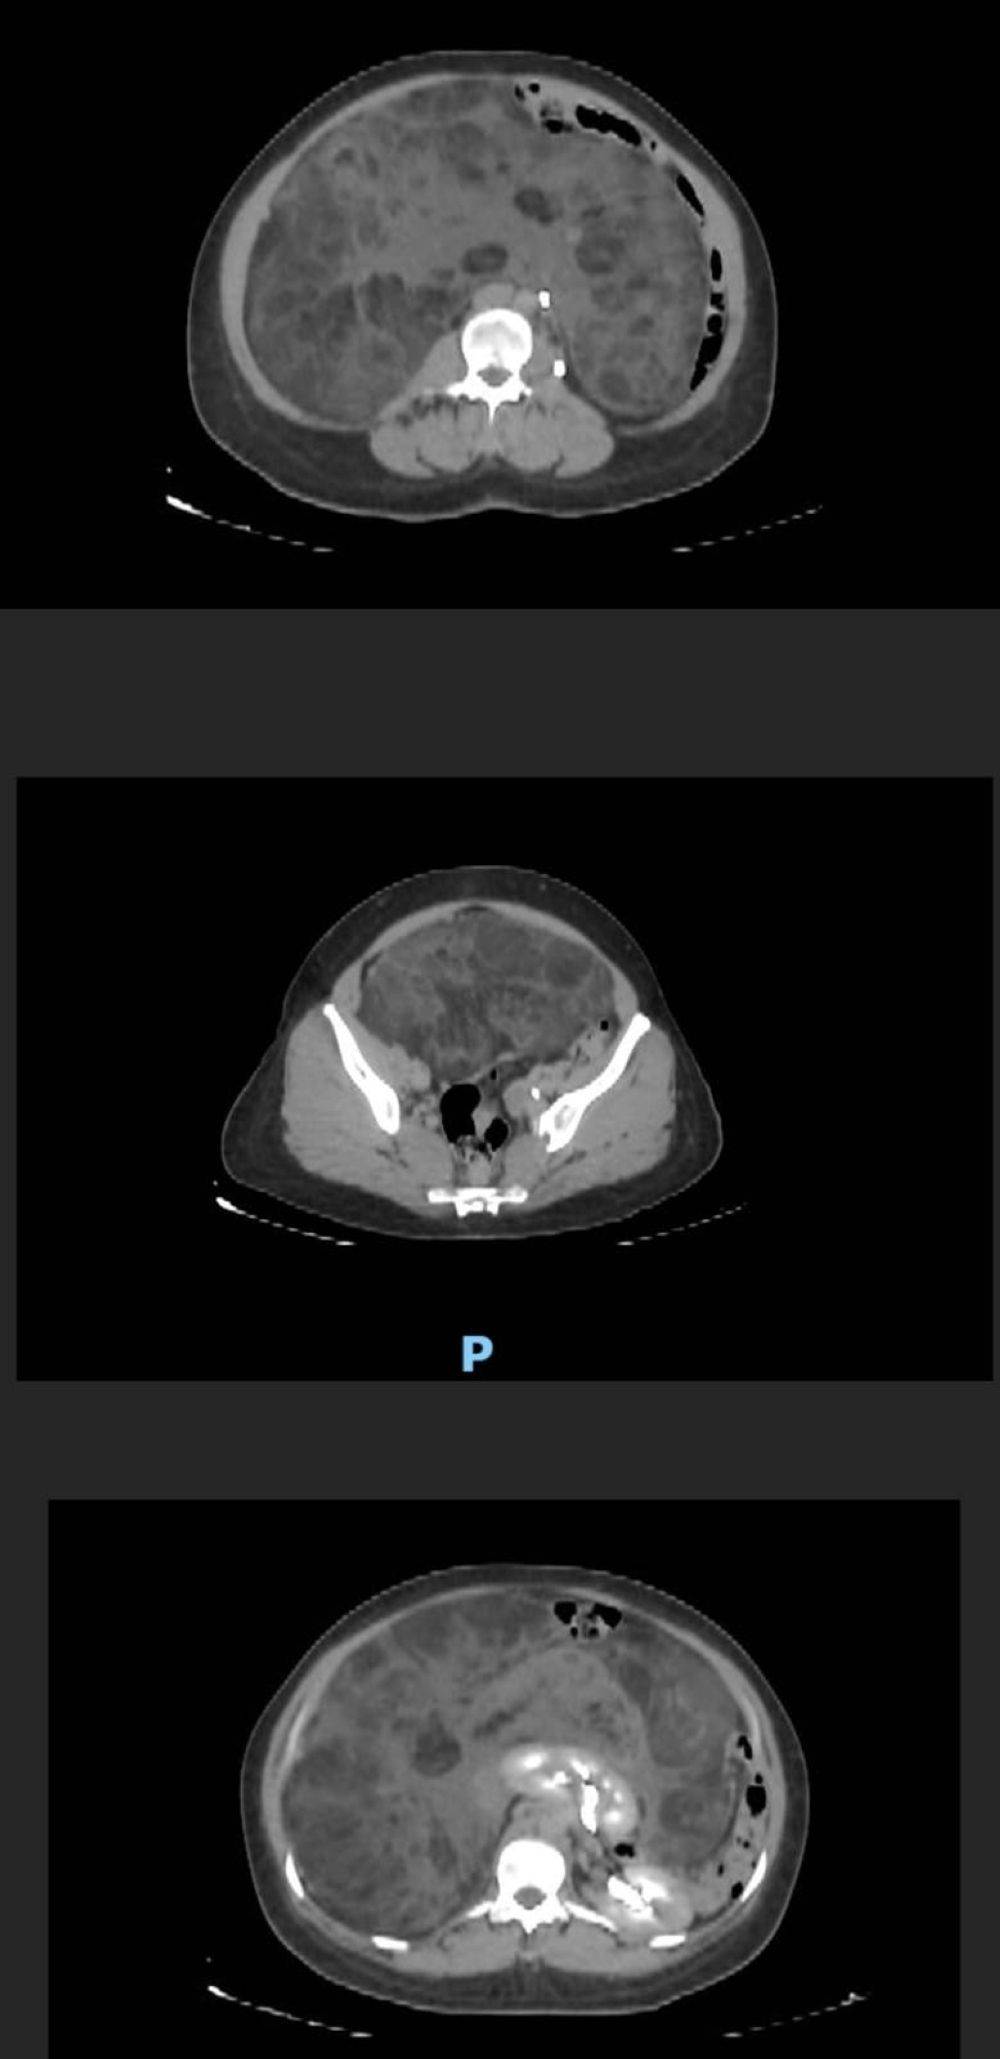

وأوضحت المدينة بأن الفريق الطبي للحالة بقيادة استشاري ورئيس وحدة جراحة أورام الجهاز العلوي والمناظير د.عبدالعزيز الربيع باشر الحالة بالفحص السريري وعمل الأشعة، تبين على إثرها وجود ورم (Sarcoma) نادر يضغط على الأعضاء الداخلية للتجويف البطني، يصل وزنه 9 كجم وبحجم ويصل إلى 45 سم كان يغطي كامل التجويف.

وأشارت المدينة إلى أن الفريق الطبي قرر إجراء عملية جراحية تبعًا للتوصيات العالمية لكبر حجم الورم وذلك لإزالته، حتى تستعيد قدرتها على العيش بشكل طبيعي وتمارس حياتها اليومية بشكل طبيعي، وتكللت -ولله الحمد- بالنجاح بدون أي مضاعفات.